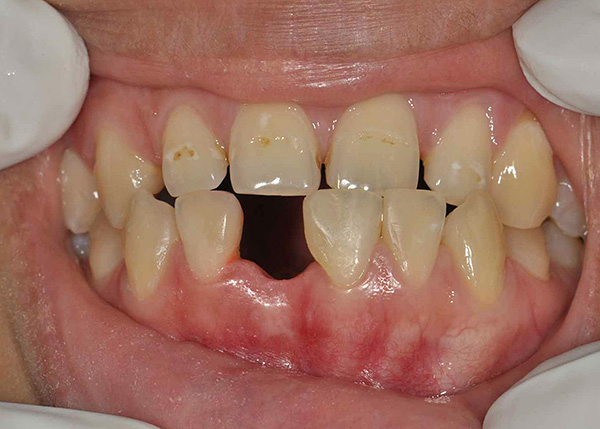

Le fotografie seguenti mostrano un esempio corrispondente (posizionamento di un impianto al posto di un dente estratto dopo la guarigione di un foro):